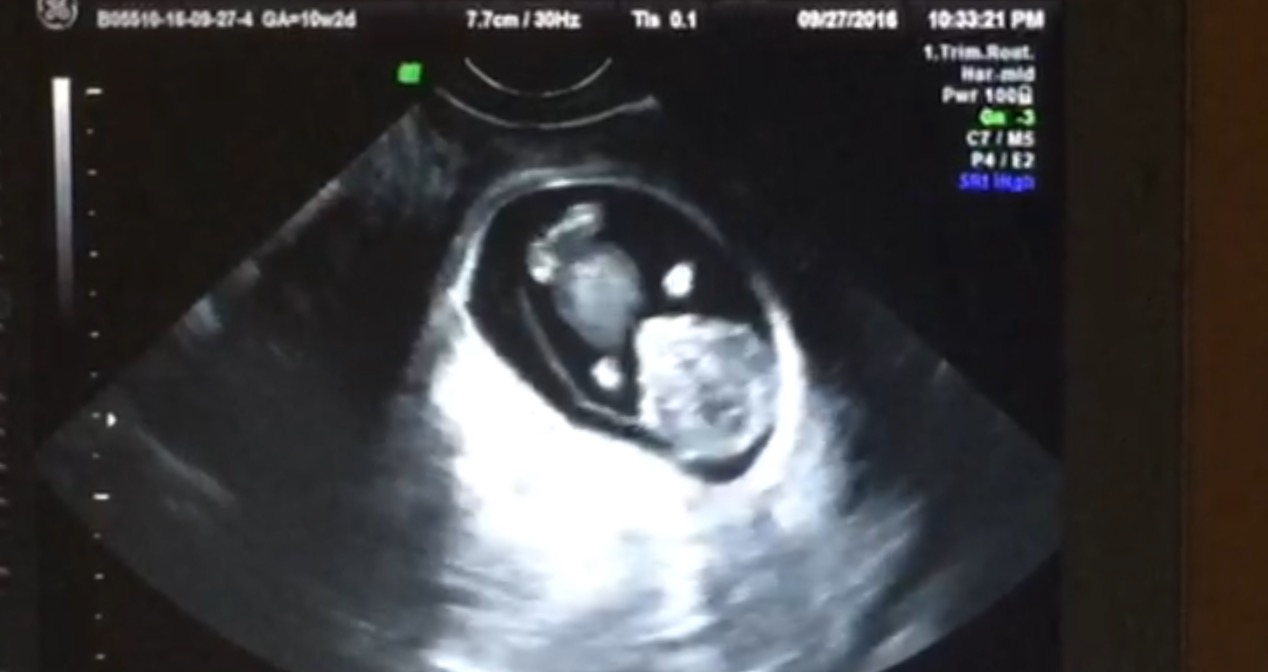

New to TB, first baby. This is our 10 week scan, and I won't have another until the anatomy scan. It's so hard to wait and wonder what's going on in there! It was pretty surreal to see the little baby moving all around during this scan. Baby loved to wiggle their little booty, and they were looking right at the 'camera' the whole time! Can't wait to see my baby again and find out if it's a boy or a girl!

New to TB as well with my first! This is from my 10 week scan last Tuesday. These are screenshots from a video we have of baby completely rolling over! So amazing to see all that wiggling!!